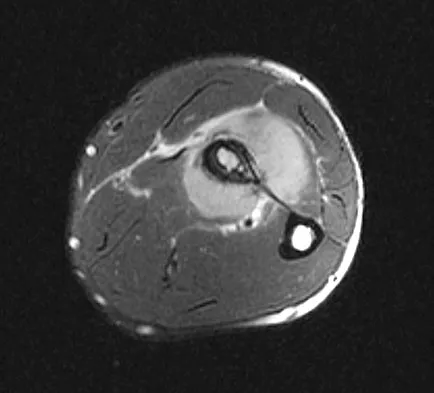

A 31-year-old woman has increasing pain and tightness in her right knee, with occasional stiffness and recurrent hemorrhagic effusions. MRI scans are shown in Figures 2a and 2b. What is the most likely diagnosis?

Explanation

PVNS is a rare inflammatory granulomatous condition of unknown etiology, and causes proliferation of the synovium of joints, tendon sheaths, or bursa. The disorder occurs most commonly in the third and fourth decades but can occur at any age. MRI provides excellent delineation of the synovial disease. Characteristic features of PVNS on MRI include the presence of intra-articular nodular masses of low signal intensity on T1- and T2-weighted images and proton density-weighted images. Synovial biopsy should be performed if there is any doubt of the diagnosis. Total synovectomy (open or arthroscopic) is required for the diffuse form, although recurrence is common. Rheumatoid arthritis and synovial chondromatosis are not typically associated with hemorrhagic effusions. De Ponti A, Sansone V, Malchere M: Result of arthroscopic treatment of pigmented villonodular synovitis of the knee. Arthroscopy 2003;19:602-607. Chin KR, Barr SJ, Winalski C, et al: Treatment of advanced primary and recurrent diffuse pigmented villonodular synovitis of the knee. J Bone Joint Surg Am 2002;84:2192-2202.